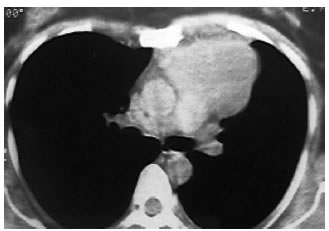

Estudios por imágenes: La tomografía computada (TC) de tórax confirma la presencia de una masa en mediastino medio (90 × 60 mm), de bordes regulares bien definidos, y densidad líquida (Figura 2). No se observan adenopatías, ni derrame pleural ni pericárdico.